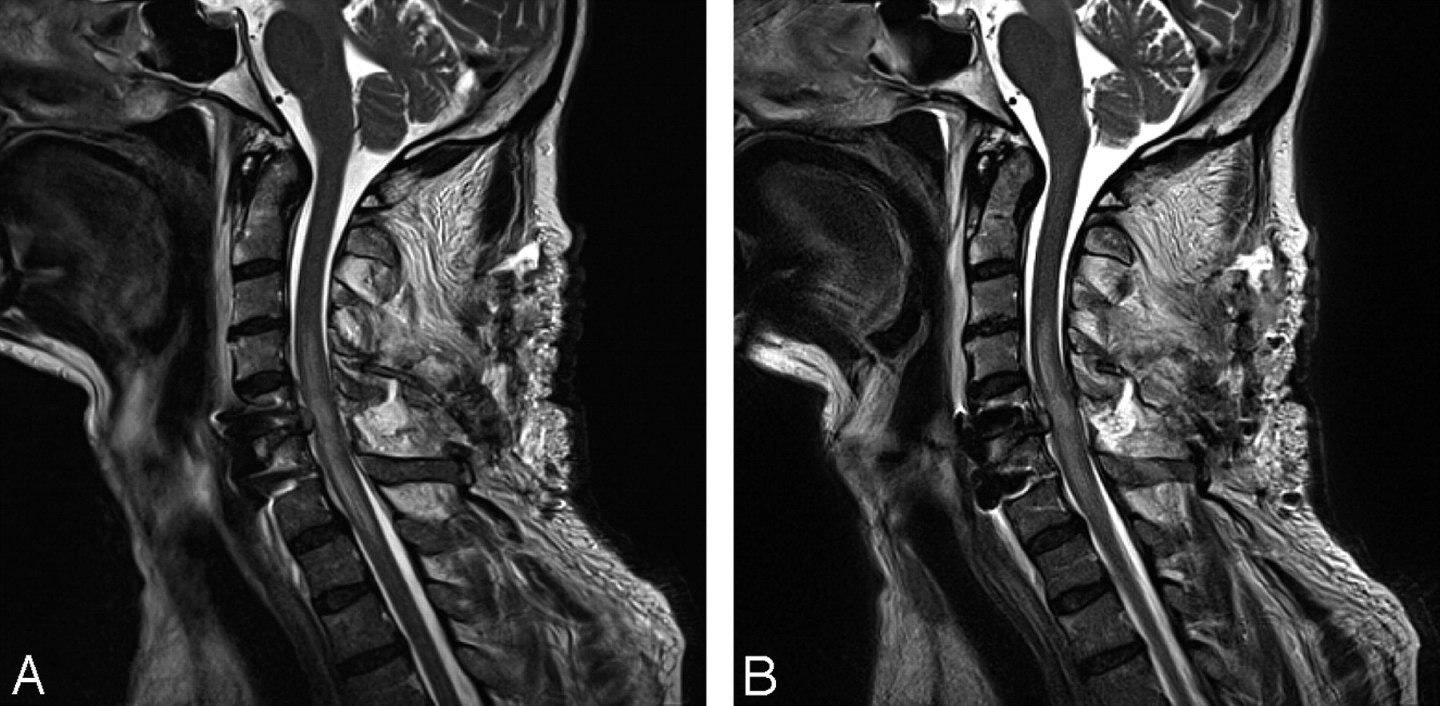

Purpose: To identify patients presenting with neck pain with cervical myelopathy based on specific patient characteristics.

1. Cook CE, et al. Clustered clinical findings for diagnosis of cervical spine myelopathy. J Man Manip Ther. 2010; 18(4): 175-180.